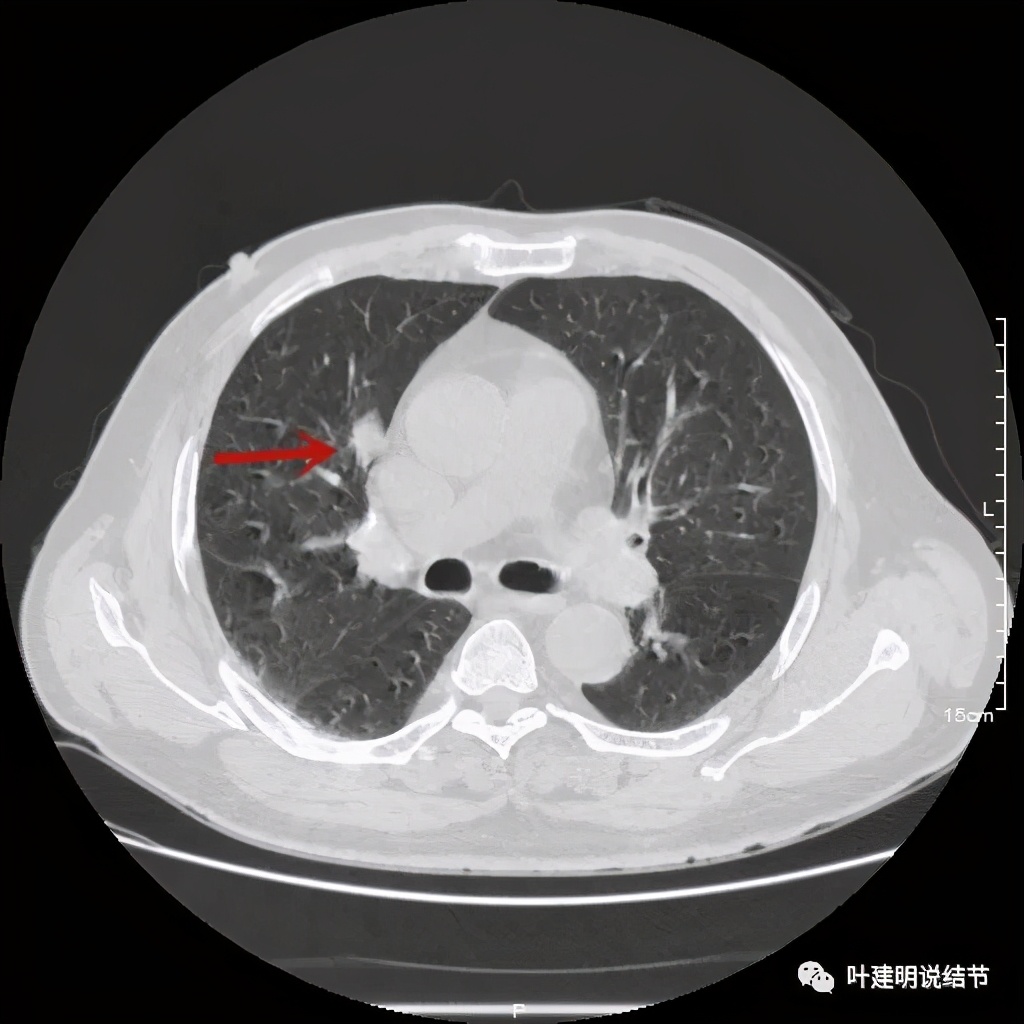

金华的某A,男性,70岁,因检查发现右上肺占位入院,没有临床症状,肿瘤筛查指标正常,血常规与CRP正常。胸部CT检查报告考虑恶性可能:

直径约2.4厘米,密度欠均,血管贴边,增强轻度强化。单从描述看,恶性可能性较大。我们再来看看图像:

可见右上叶占位,我们现在知道了结果以后回头看,发现病灶的边缘在各个层面都是过于光滑(绿色箭头所示)。血管紧贴病灶边走行(桔色箭头所指),是不是有侵犯看不清楚,若是靶扫描加重建可能会更清楚点。支气管感觉也是贴着病灶走,但有的层面是不是截断,也不看的不太清楚。有的层面见局部有点状高密度(蓝色箭头所指),是不是错构瘤的局部钙化呢?若是纵隔窗又是如何?

上图示病灶

上图示病灶密度不均